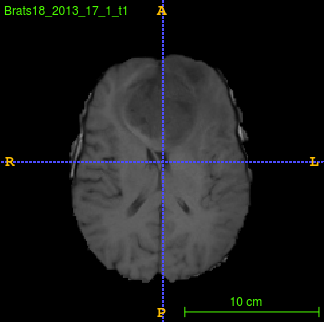

Segmentation of brain tumor from magnetic resonance imaging (MRI) is a vital process to improve diagnosis, treatment planning and to study the difference between subjects with tumor and healthy subjects. In this paper, we exploit a convolutional neural network (CNN) with hypercolumn technique to segment tumor from healthy brain tissue. Hypercolumn is the concatenation of a set of vectors which form by extracting convolutional features from multiple layers. Proposed model integrates batch normalization (BN) approach with hypercolumn. BN layers help to alleviate the internal covariate shift during stochastic gradient descent (SGD) training by zero-mean and unit variance of each mini-batch. Survival Prediction is done by first extracting features(Geometric, Fractal, and Histogram) from the segmented brain tumor data. Then, the number of days of overall survival is predicted by implementing regression on the extracted features using an artificial neural network (ANN). Our model achieves a mean dice score of 89.78%, 82.53% and 76.54% for the whole tumor, tumor core and enhancing tumor respectively in segmentation task and 67.90% in overall survival prediction task with the validation set of BraTS 2018 challenge. It obtains a mean dice accuracy of 87.315%, 77.04% and 70.22% for the whole tumor, tumor core and enhancing tumor respectively in the segmentation task and a 46.80% in overall survival prediction task in the BraTS 2018 test data set.